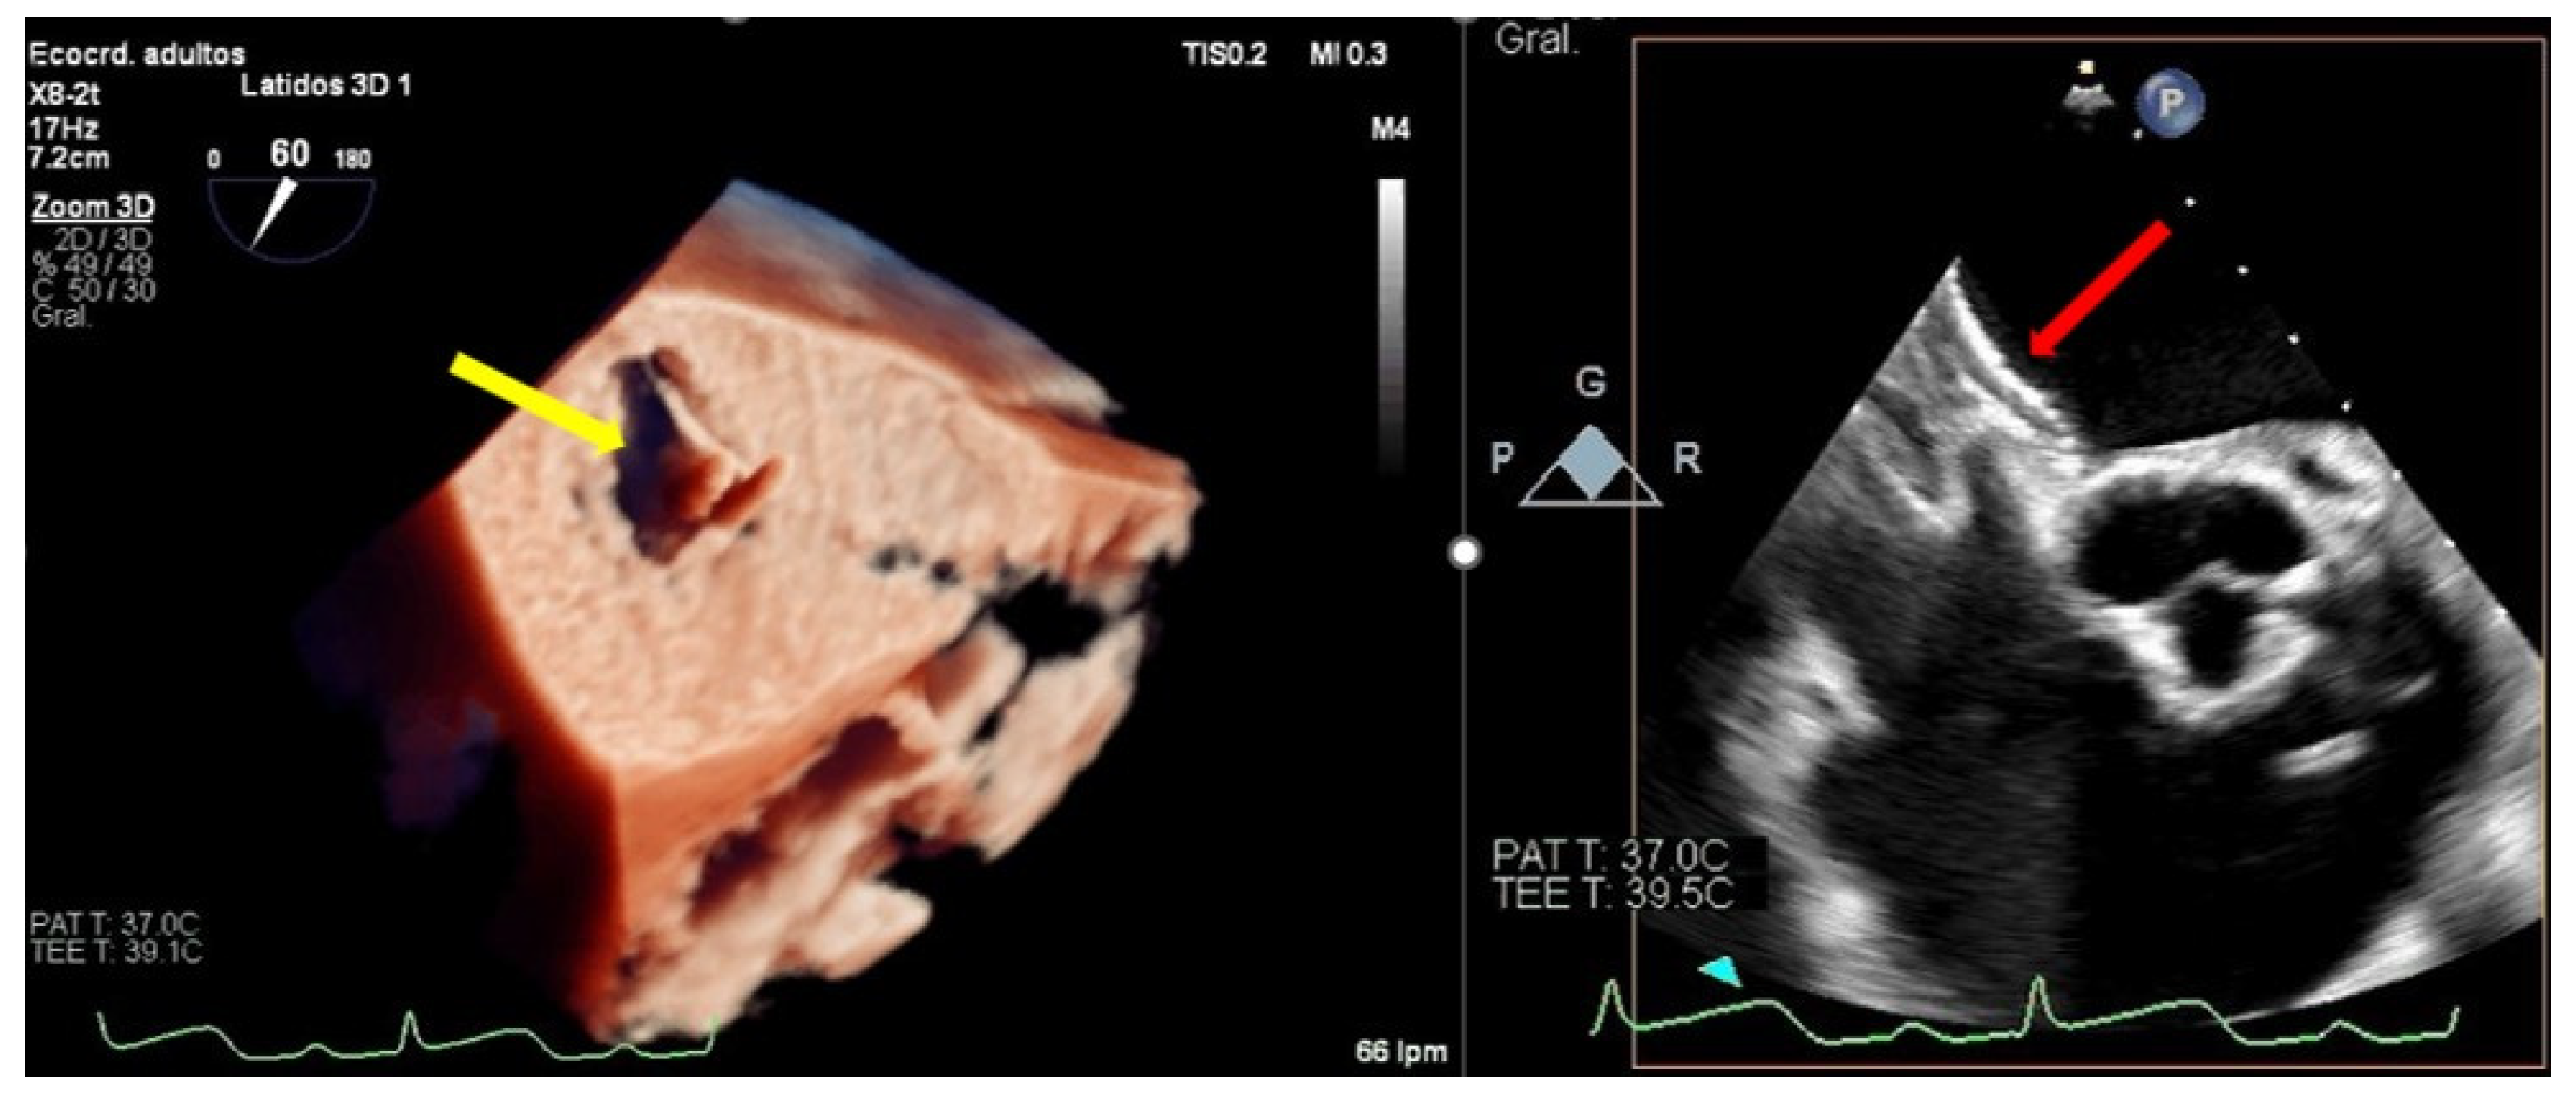

The echocardiographic criteria to diagnose SLDA are the color Doppler demonstration of significant MR through the leaflet interface, new excessive leaflet mobility following device deployment, and a lack of diastolic tissue bridge by 3DTEE; acute changes in pressure also occur with the new appearance of the v-wave after the initial improvement after clip implantation (Figure 5). Once the complication has occurred, the TEE undoubtedly helps in determining the mechanism of the loosening of the leaflet by measuring the portion of the free leaflet with respect to the measurement prior to implantation [13]. Other mechanisms, such as tear or perforation, can be viewed as a disruption of leaflet integrity reaching the leaflet edge or not, respectively. An excessive clip–leaflet tension can be shown as a shape distortion affecting leaflet coaptation, without disruption of the leaflet integrity. The entrapment of the clip in leaflets or subvalvular structures with chordal rupture appears in TEE as new excessive leaflet mobility [1]. Chordal entanglement should be avoided by minimizing device manipulation below the mitral valve and not advancing the system deep into the left ventricle.

Figure 5.

Two-dimensional transesophageal echocardiogram showing a very severe mitral regurgitation after the partial detachment of a clip and a leaflet tear prolapsing in the left atrium (yellow arrow). Three-dimensional transesophageal echocardiogram in the enface mitral view, where a clip can be seen attached to the anterior leaflet (red arrow) and loose from the posterior with a lack of diastolic tissue bridge. In the lower panel, simultaneous recording of left atrium (green), pulmonary artery (yellow), and aortic pressure (purple): baseline, post clip implantation and after detachment.